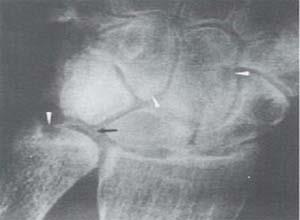

简介黏多糖贮积症Ⅶ型又称戈尔伯杰(Goldberg)综合征,β-葡萄糖苷酸酶缺乏症。其特征为智力正常或略落后、骨骼改变,特殊面容、侏儒、肝脾肿大和有疝气,尿中可以排出过多硫酸皮肤素,为一种常染色体隐性遗传病,虽然生化缺陷相同,但各例的临床表现和起病年龄皆有不同。